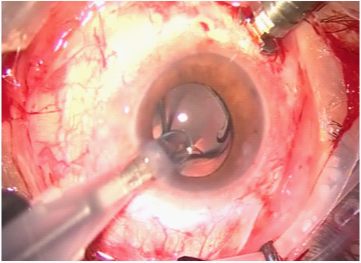

Cataract (Figure 6)

Figure 6 Phacoemulsification & foldable IOL in bag.

1. Phacoemulsification & foldable IOL in the bag

2. Keep the AC pressure always higher than the posterior segment.

3. Avoid extensive dialing of the IOL.

4. Keep the anterior chamber filled with healon to avoid passage of silicone oil to the anterior chamber during posterior segment work (Figure 7).